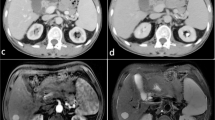

Contrast-enhanced CT dataset of 40 patients (n = 40; M:F = 5:3; age = 25–55 years) with three groups of subjects: healthy (n = 14), cirrhosis (n = 12) and cirrhosis with HCC (n = 14), were retrospectively analyzed in this study. A novel method for the automatic 3D segmentation of liver using modified region-growing segmentation technique was developed and compared with the state-of-the-art deep learning-based technique. Further, histogram parameters were calculated from segmented CT liver volume for classification between healthy and diseased (cirrhosis and HCC) liver using logistic regression. Multi-phase analysis of CT images was performed to extract 24 temporal features for detecting cirrhosis and HCC liver using support vector machine (SVM).

The proposed method produced improved 3D segmentation with Dice coefficient 90% for healthy liver, 86% for cirrhosis and 81% for HCC subjects compared to the deep learning algorithm (healthy: 82%; cirrhosis: 78%; HCC: 70%). Standard deviation and kurtosis were found to be statistically different (p < 0.05) among healthy and diseased liver, and using logistic regression, classification accuracy obtained was 92.5%. For detecting cirrhosis and HCC liver, SVM with RBF kernel obtained highest slice-wise and patient-wise prediction accuracy of 86.9% (precision = 0.93, recall = 0.7) and 80% (precision = 0.86, recall = 0.75), respectively, than that of linear kernel (slice-wise: accuracy = 85.4%, precision = 0.92, recall = 0.67; patient-wise: accuracy = 73.33%, precision = 0.75, recall = 0.75).